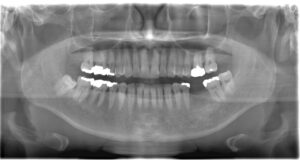

下の参考写真をご覧ください。パノラマエックス線写真というのは、日本の歯科医院でよく撮影されるものです。短時間で撮影でき、全体を把握するのに向いています。この方の場合、パノラマエックス線写真ではむし歯が見当たらず、直接口腔内を見てもむし歯は確認できませんでした。ところが、当院でバイトウイングを撮影したところ、パノラマエックス線写真や目視では確認できなかったむし歯が見つかりました。このようなむし歯は「隠れむし歯」と呼ばれ、気づくのが遅れるとかなり進行してしまいます。

【参考写真】パノラマエックス線写真とバイトウイングでのむし歯の見え方の違い

パノラマエックス線写真